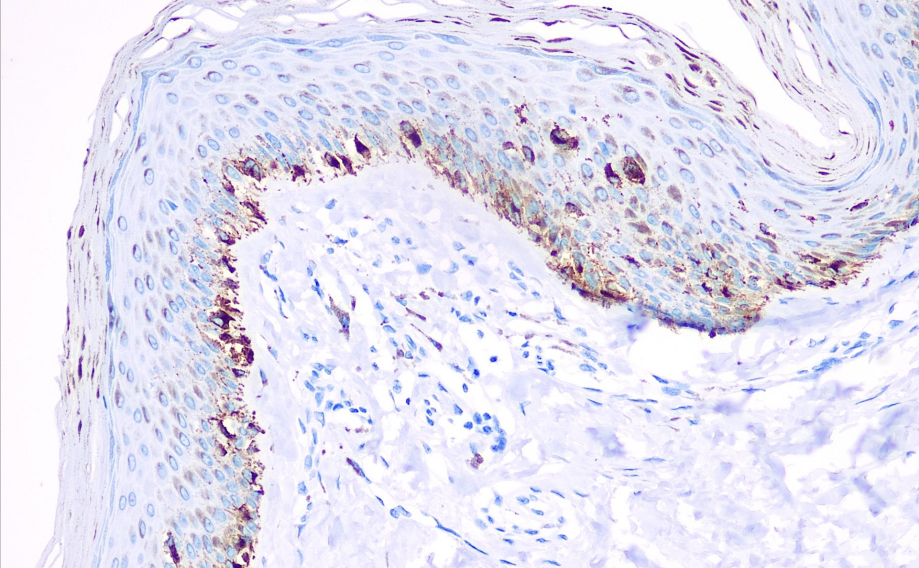

Positive Control: Skin

Tyrosinase, also known as mono-phenol mono-oxidase, catalyzes the oxidation of phenolic compounds (such as tyrosine) and is widely distributed in both plants and animals. Tyrosinase plays a catalytic role in the synthesis of melanin and other pigments and is present in melanosomes. Mutations in its gene can lead to Type I oculocutaneous albinism (incidence rate of 1 in 17,000). This antibody is specifically expressed in melanin-containing pathological tissues, such as malignant melanoma and neurofibromas associated with melanin lesions. It is not expressed in epithelial-derived cancers.

Tyrosinase antibody reagents can specifically bind to tyrosinase molecular antigens. Immunohistochemistry kits containing tyrosinase antibody reagents are suitable for the precise diagnosis of melanoma.